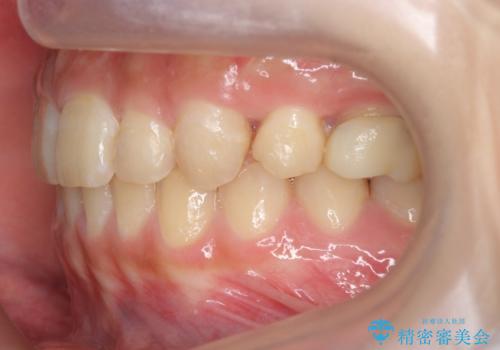

前歯のがたつき 過蓋咬合

- 上の小臼歯を2本抜歯して矯正を行いました。

今回は上の前歯が内側に傾いている症状があり(Angle Ⅱ級2類)、その修正に時間がかかっています。

一見同じような歯並びに見えても、前歯の角度や、奥歯の上下の噛み合わせによって難易度には差があります。